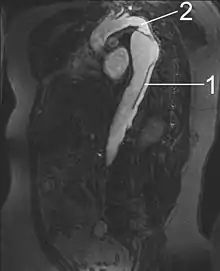

By separating a portion of the wall of the artery (a layer of the tunica media or in some cases tunica intima), a tear creates two lumens or passages within the vessel, the original or true lumen, and the false lumen created by the new space within the wall of the artery. It is not yet clear if the tear in the innermost layer, the tunica intima, is secondary to the tear in the tunica media. Dissections originating in the tunica media are caused by disruption of the vasa vasorum. It is thought that dysfunction in the vasa vasorum is an underlying cause of dissections.[2]